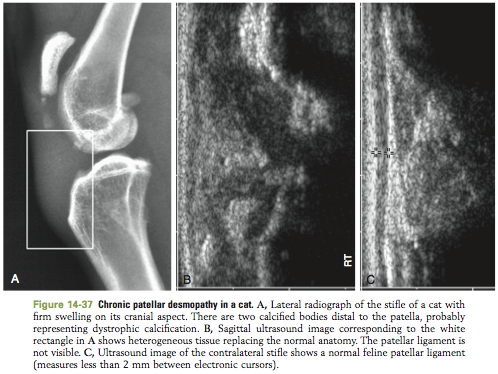

Tendons and Ligaments